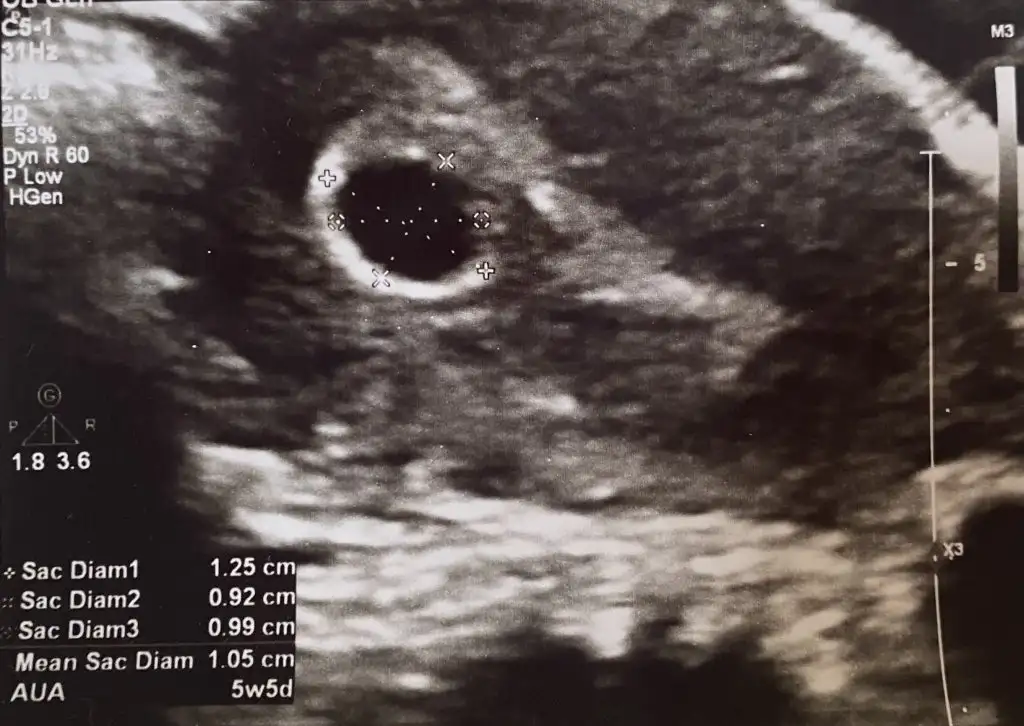

Ultrasonun kalitesi bile etkiliyor ya zamanı, görece daha eskiyse o bile duymanı engelleyebilir. Yolk sac vs görünmüştür belki ondan boş değildir demiştir kalbini ferah tutSelam kizlar ilk ultrasonuma 5+3 te girmistim kese gorunmustu dun 6+2 de tekrardan girdim tekrardan kese gorundu doktora cogu 6. Haftasinda kalp atisini duyuyo bende bebek henuz gorunmuyo bos gebelik mi acaba dedim hayir bos gebelik degik 5 6. Haftalarda kese gorunur 8. Haftada kalp atisi duyulur dedi ultrasonda biseyler gosterip bak yeni olusmaya basliyo dedi vajinal ultrason yapmadi ne oldugunu soramadin o an haftaya yine cagirdi benim durumumu yasayan var mi?